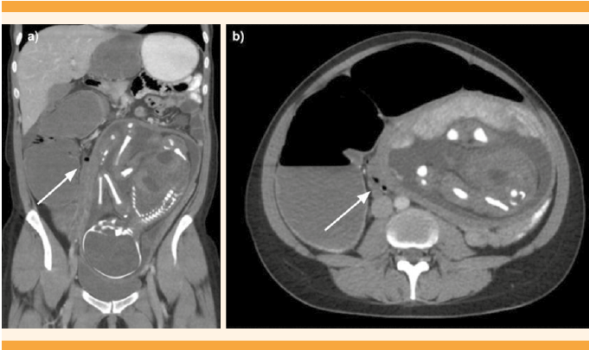

Evolucionó con incremento del dolor abdominal y, ante la presunción diagnóstica de oclusión intestinal, se practicó una TAC que despertó la sospecha de vólvulo colónico (Figura 2). Debido a la estabilidad hemodinámica y a la ausencia de signos de peritonitis, se decidió una videocolonoscopia que reveló la imagen característica en “remolino” de los pliegues mucosos del colon. Durante la misma, se colocó una sonda descompresiva con desaparición inmediata del cuadro oclusivo. Figura 3

a. Corte coronal. Se observa el útero con el feto ocupando la mayor parte del abdomen. Transición de calibre a nivel del colon descendido en la cirugía previa, con dilatación proximal del colon (flecha). b. Corte axial. Colon distendido con afinamiento de su calibre hacia distal (flecha).

Figura 2 TAC.